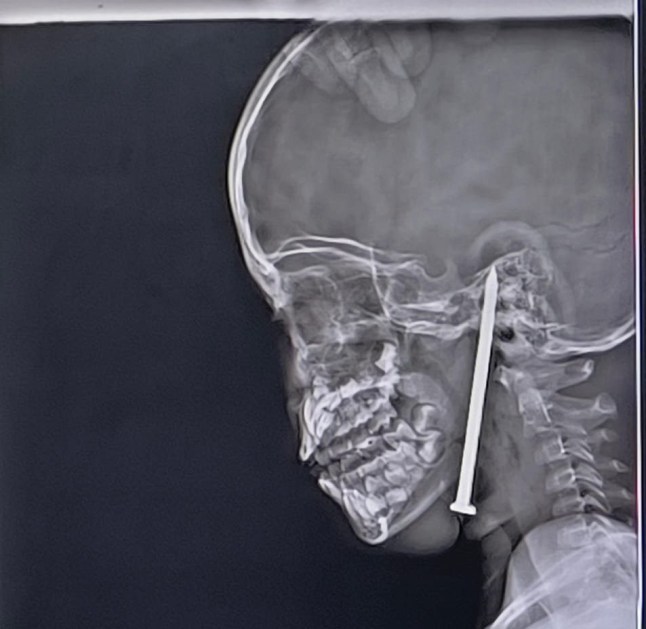

X-ray images showed the nail lodged inside the base of the girl’s head (Picture: SWNS)

The seven-year-old,from a village in the state of Uttar Pradesh,was taken to hospital on May 15 with the construction nail lodged inside her head.

It had pierced her neck,passing below the jaw and through the palate into the cranial cavity,where it partially entered her brain.

The nail had travelled through the neck and palate (Picture: SWNS)